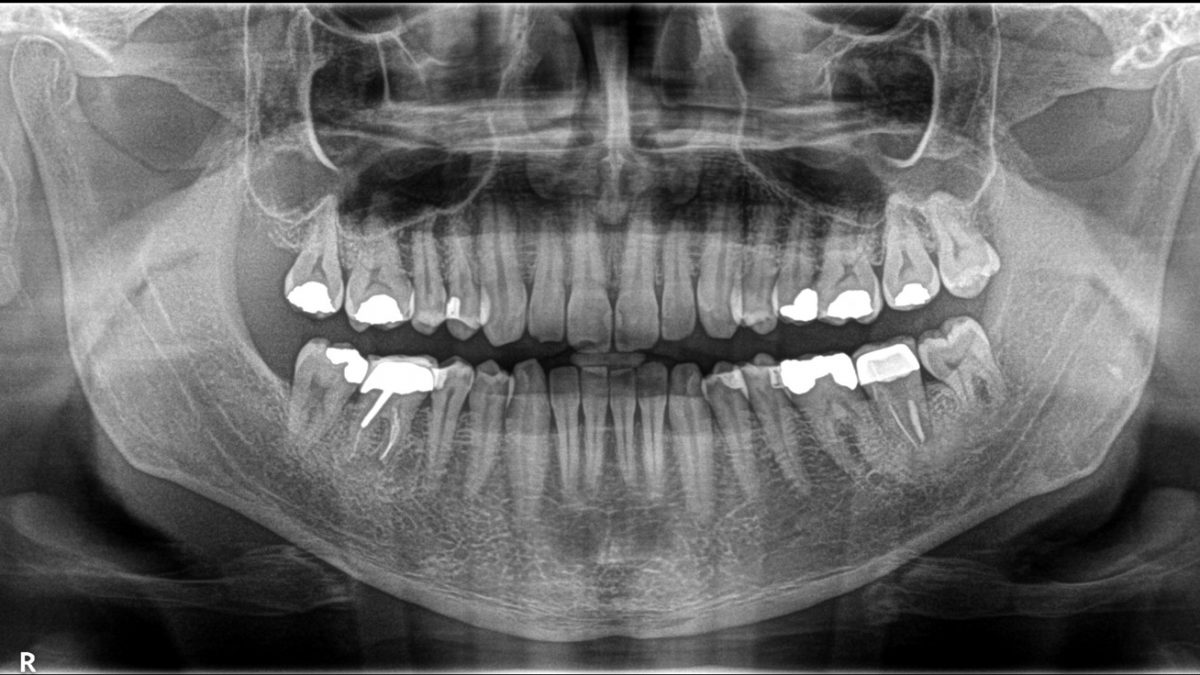

رادیوگرافی اولیه که نشان دهنده رویش کامل دندانهای عقل در سمت راست تصویر و عدم نیاز ان ها به کشیدن میباشد. در سمت چپ دندانهای عقل به علت کمبود فضا و عدم رویش کامل قبلا کشیده شده بودند.